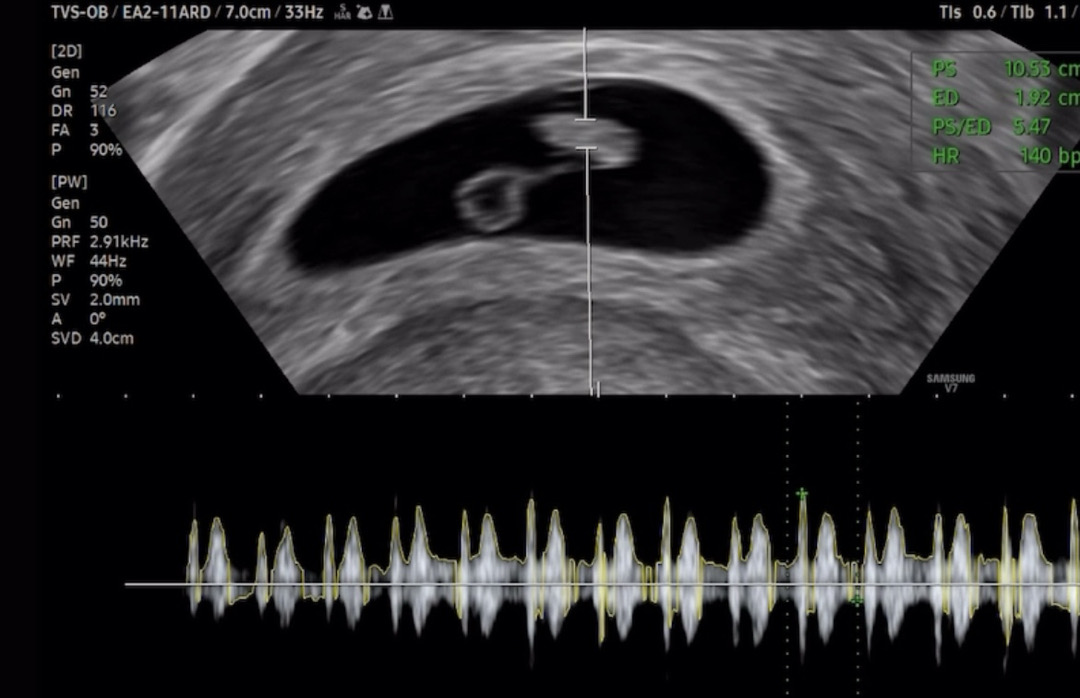

7주차 초음파

안녕하세요 어제 7주차 초음파 보고왔습니당 아기 크기는 0.94cm, 심박수는 140bpm이라고 하셨는데 생예 막날 기준으로는 7주 2일인데 초음파는 7주 0일로 나왔네용 이틀 차이는 괜찮은거죠? 그리고 난황도 좀 커보이고 난황과 아기 사이가 떨어져있는데 이것도 괜찮은건가요? 선생님은 별다른 말씀 없으셨는데 괜히 걱정돼서 질문드려봅니당..!

일주일 차이 나도 상관 없어요 커가는 크기에 따라 초음파에서 보이는 예정일은 계속 조금씩 다를 수 있으니 신경 안 쓰셔도 돼요 난황과 멀어보이는 것도 아무 문제 없어요 아기랑 잘 연결되어 있어서 영양분 받는데는 이상이 없습니다